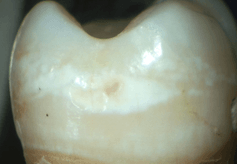

在牙侵蚀症的早期阶段,牙釉质表层会被侵蚀掉,而在后期阶段,就会使得较柔软的牙质甚至牙齿中央柔软的部分(牙髓)裸露出来。

(在牙侵蚀症的)早期阶段,牙侵蚀症会造成牙齿对冷食物敏感。如果发展下去,接下来可能会造成更严重的疼痛。并不是所有的无糖口香糖都包含食品酸味剂,通常来讲,相比其他口味的口香糖,薄荷味口香糖造成侵蚀的可能性要小些。

(牙侵蚀症)早期阶段

牙侵蚀症—由于酸侵蚀对牙齿造成的不可逆损伤。